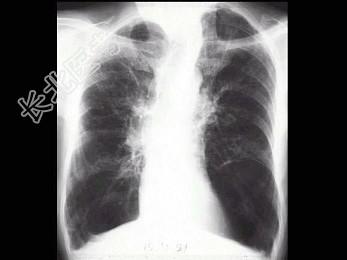

- 单项选择题男,65岁, 呼吸困难伴胸闷1月余,胸片如图, 最可能的诊断为 ( )

A、气胸

B、肺结核

C、慢性支气管炎并肺气肿

D、肺部感染

E、支气管扩张